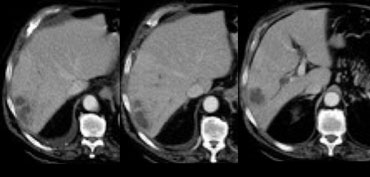

Flash filling hemangioma in unenhanced, arterial and portal venous phase. Notice it matches the bloodpool. Flash filling hemangioma in unenhanced, arterial and portal venous phase. Notice it matches the bloodpool.

Small hemangiomas may show fast homogeneous enhancement ('flash filling').

Small HCC and hypervascular metastases may mimic small hemangiomas because they all show homogeneous enhancement in the arterial phase.

By looking at the other phases to see if the enhancing areas match the bloodpool, it is usually possible to differentiate these lesions.